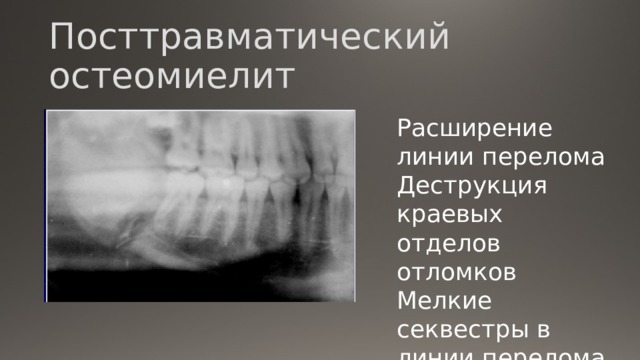

Рентгеновские снимки посттравматического остеомиелита челюсти: Медицинские случаи